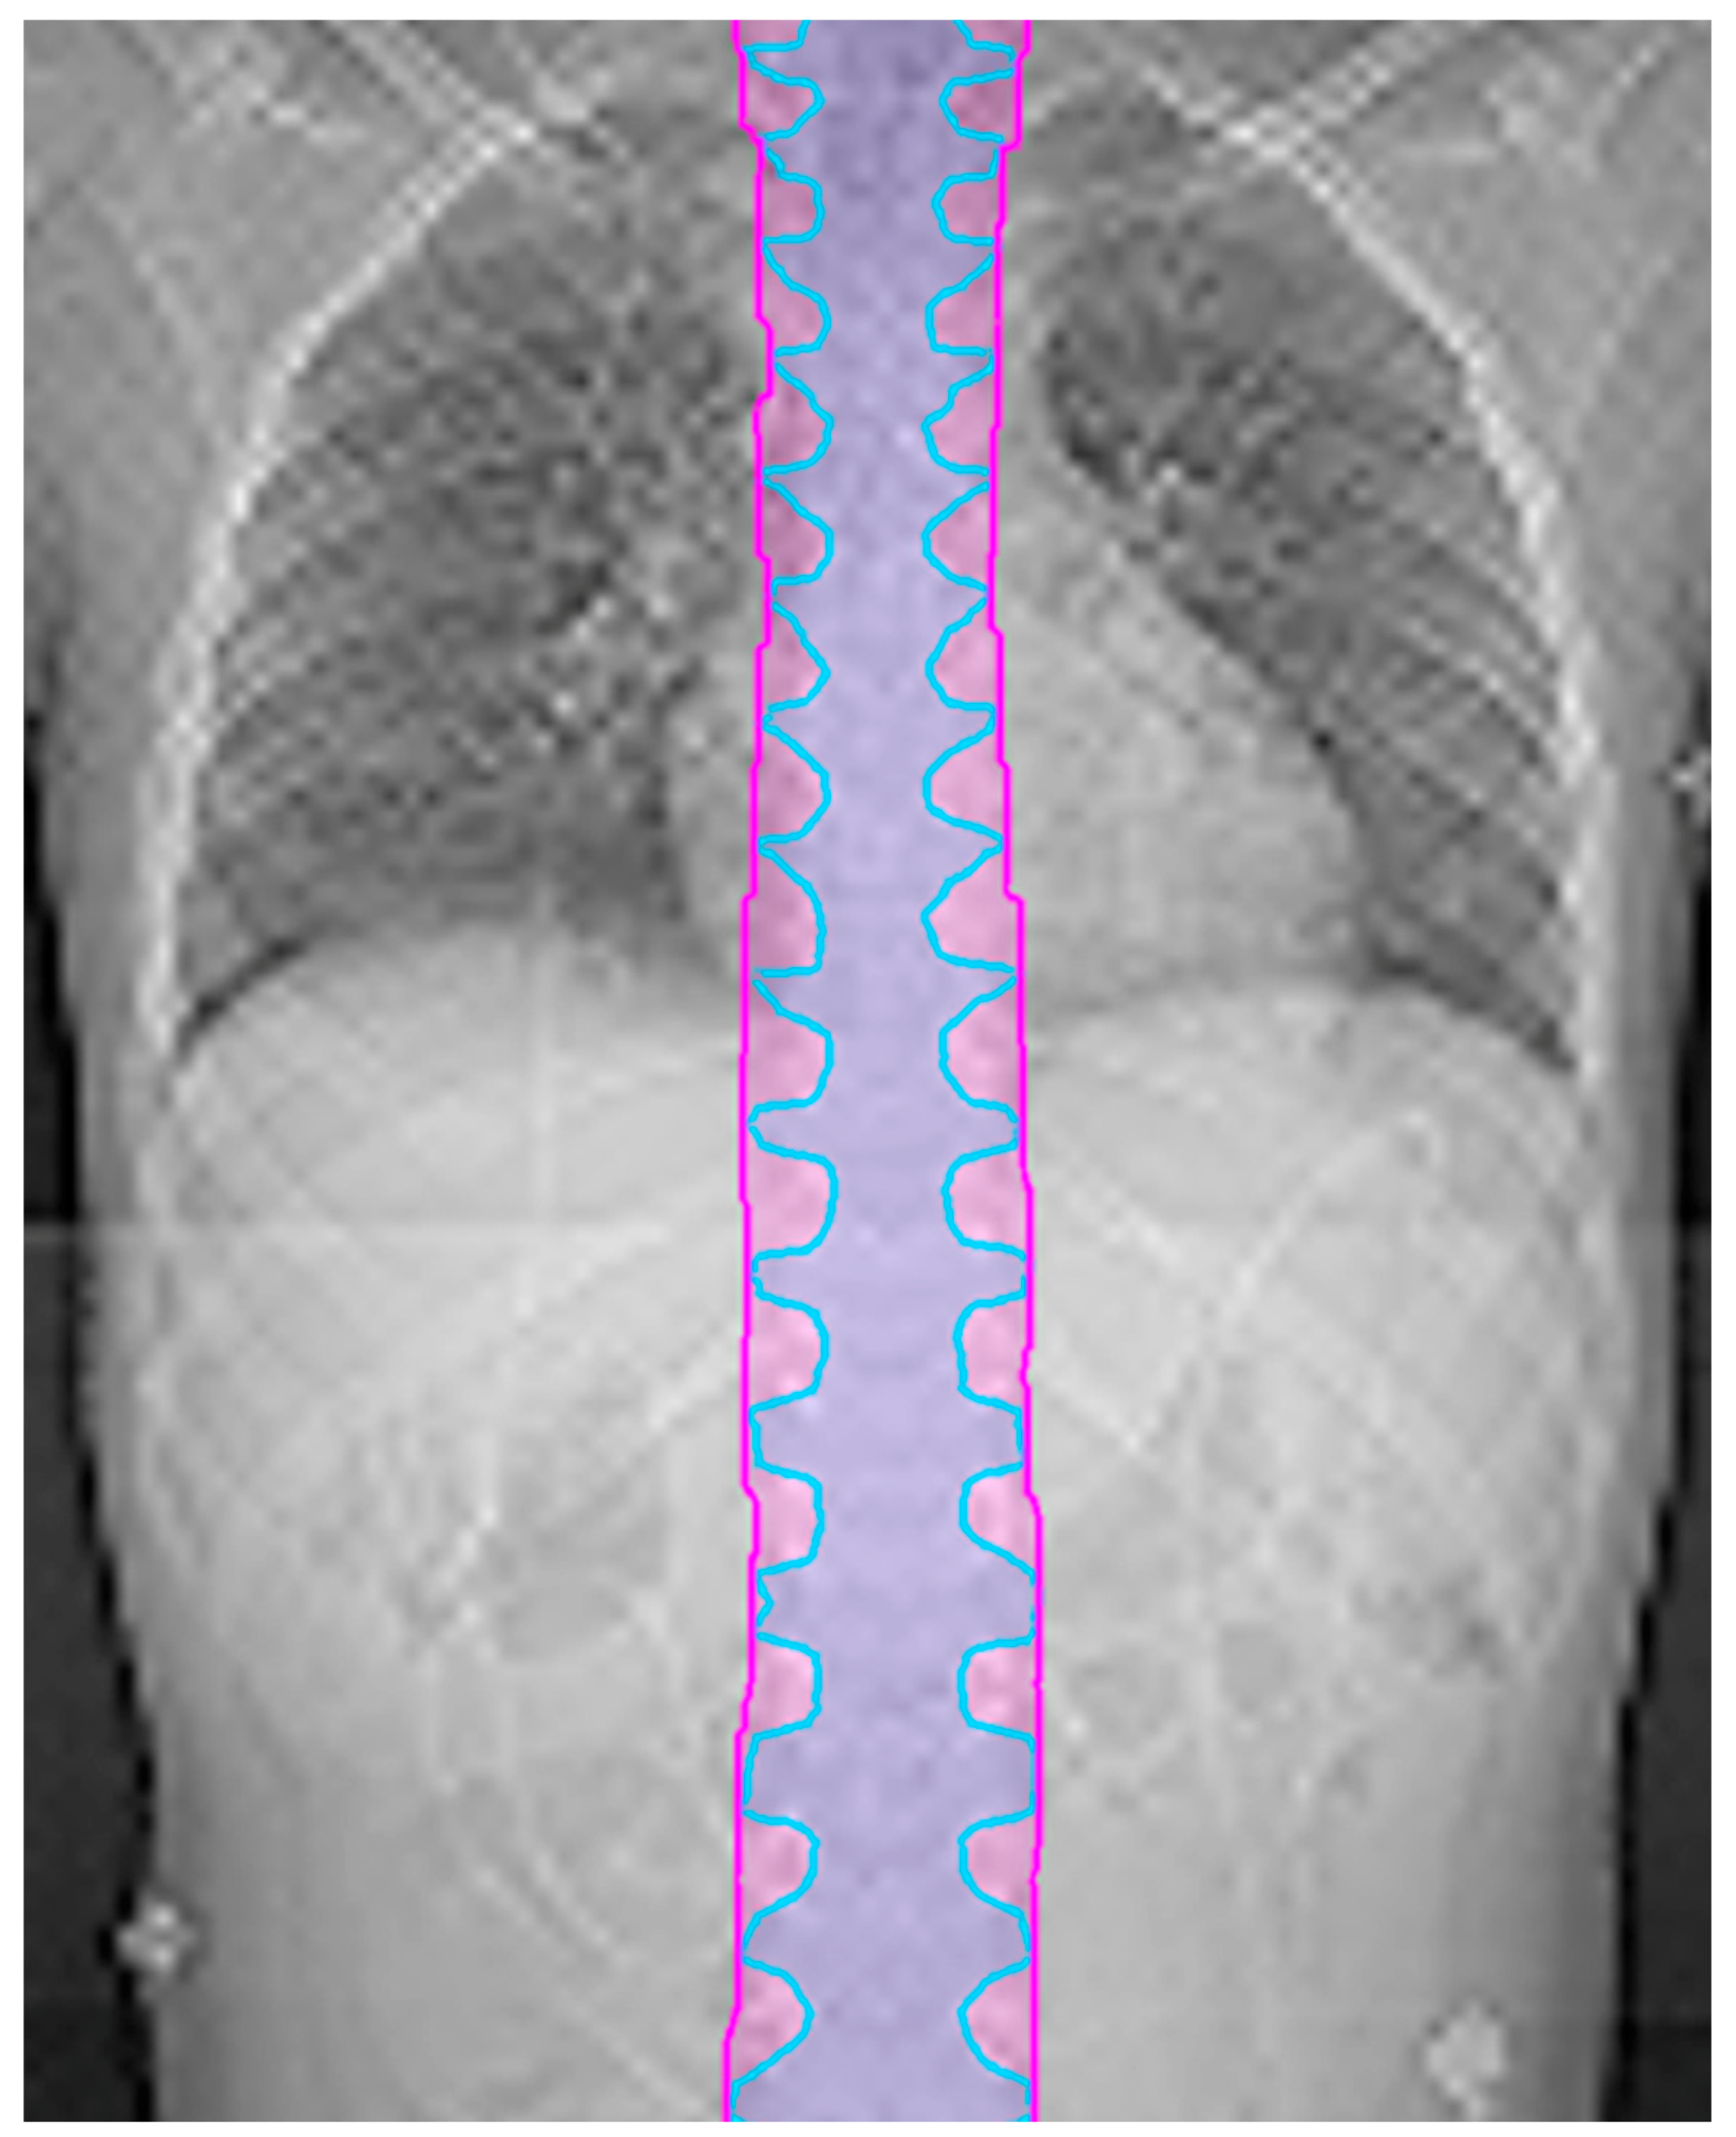

In younger patients, where it is recommended that the entire vertebral body be treated to promote uniform growth [9], it is possible that nearby critical structures will get an undesired dose. A higher priority is given to esophagus and constrictor sparing than vertebral body coverage. When vertebral body coverage is forfeited in lieu of critical structure sparing, it is desired to have the dose form a straight line across the vertebral body, as shown in Figure 2, to promote uniform lateral growth of the bone. The pros and cons of sparing the esophagus vs. symmetric anterior to posterior irradiation of the vertebral body must be considered. To achieve this, a non-uniform PRV is created by forming a box around the esophagus and constrictors with expansions of 5 mm anterior–posterior and 5 cm left–right. The dose is pushed out of this PRV box structure to achieve the lowest dose possible to the esophagus and constrictors without affecting CTV coverage, noting that the vertebral body will have an anterior–posterior gradient, but not a right–left gradient. The esophagus sparing is important for high risk patients with a prescription of 36 GyE, but may be less so for low risk patients with a prescription less than 24 GyE.

Figure 2. When compromising vertebral body coverage to spare the esophagus (orange circle), it is desired to have the dose form a straight line across the vertebral body. A box drawn around the esophagus (purple shaded line/area) is used to create this dose distribution. Note the prescription is 36 Gy.